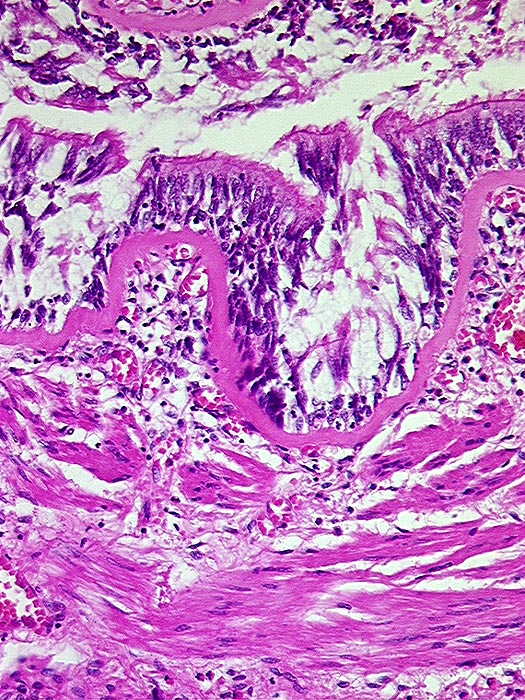

AP/ Asthma bronchiale

Asthma bronchiale

Bronchus

Pathologischer Befund